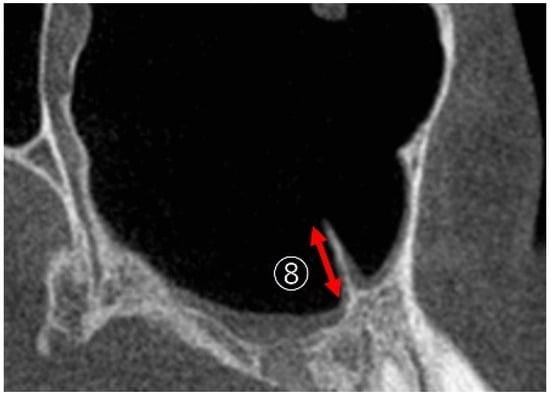

2.3.1. Linear Measurements of Maxillary Sinus Height

2.3.2. Measurement of PNR Angle and Maxillary Sinus Angle (MSA)

2.3.4. Linear Measurements of Maxillary Sinus Length